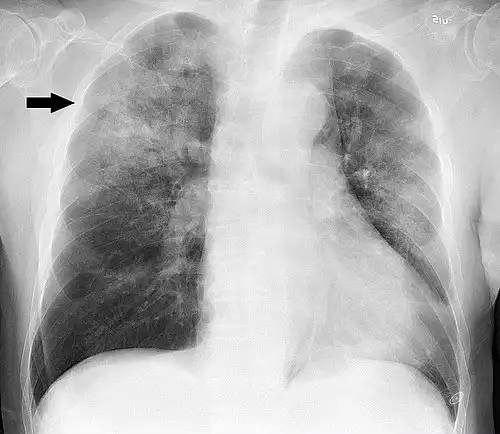

سینه پهلو یا پنومونی ( به فرانسوی: Pneumonie )، یک بیماری التهابی ریه است که عمدتاً کیسه های هوایی ( آلوئول ) تحت تأثیر قرار می دهد علائم معمولاً شامل ترکیبی از سرفه های مولد یا خشک، درد قفسه سینه، تب و تنگی نفس می شود. شدت بیماری متغیر است.

سینه پهلو معمولاً در اثر عفونت با ویروس ها یا باکتری ها و کمتر توسط سایر میکروب ها ایجاد می شود. شناسایی بیماری زا مسئول ممکن است دشوار باشد. تشخیص اغلب بر اساس علائم و معاینه فیزیکی است. رادیوگرافی قفسه سینه، آزمایش خون و کشت خلط ممکن است به تأیید تشخیص کمک کند. این بیماری ممکن است بر اساس محل کسب آن طبقه بندی شود، مانند سینه پهلو اکتسابی در جامعه یا بیمارستان یا مرتبط با مراقبت های بهداشتی.